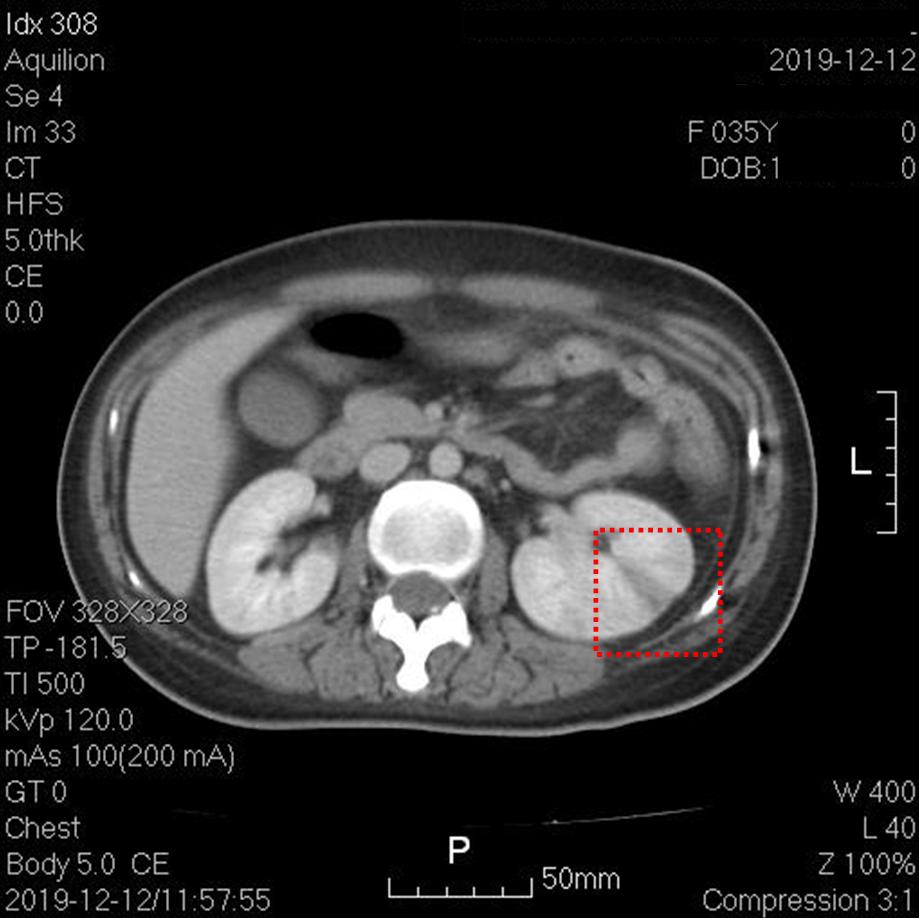

上图红框内为左肾梗死。其他层面右肾也可见楔形低密度灶。